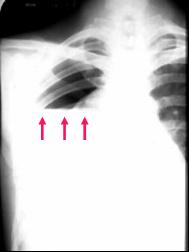

A straight edge,

indicative of a fluid

interface, in this

case an air-fluid

interface, is seen on

the right.

In order to have an

air-fluid level in the

pleural space, there

must be a

pneumothorax

present.

Hydropneumothorax